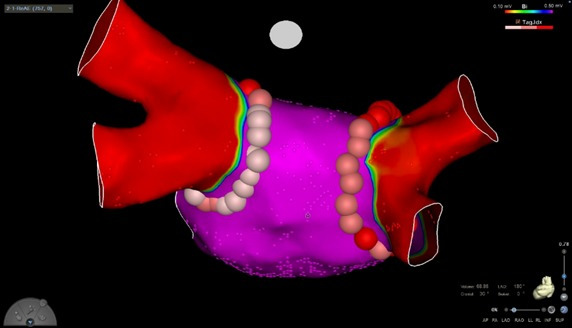

O político deve passar por novos exames neste sábado, 30. Segundo o boletim, o ex-governador estava internado devido a um quadro de “flutter atrial”. Trata-se de um funcionamento irregular do ritmo cardíaco. É caracterizado por sintomas como palpitação e, às vezes, fraqueza, intolerância a esforço e dispneia.

O ex-governador de Goiás Marconi Perillo (PSDB), internado desde a última quarta-feira ,27, no Hospital Sírio-Libanês, em São Paulo, foi submetido a um procedimento médico para tratar arritmia cardíaca na noite de sexta-feira 29.

De acordo com o boletim médico divulgado pelo hospital, o procedimento ocorreu com sucesso e não teve intercorrências. Veja abaixo:

O político deve passar por novos exames neste sábado, 30. Segundo o boletim, o ex-governador estava internado devido a um quadro de “flutter atrial”. Trata-se de um funcionamento irregular do ritmo cardíaco. É caracterizado por sintomas como palpitação e, às vezes, fraqueza, intolerância a esforço e dispneia.